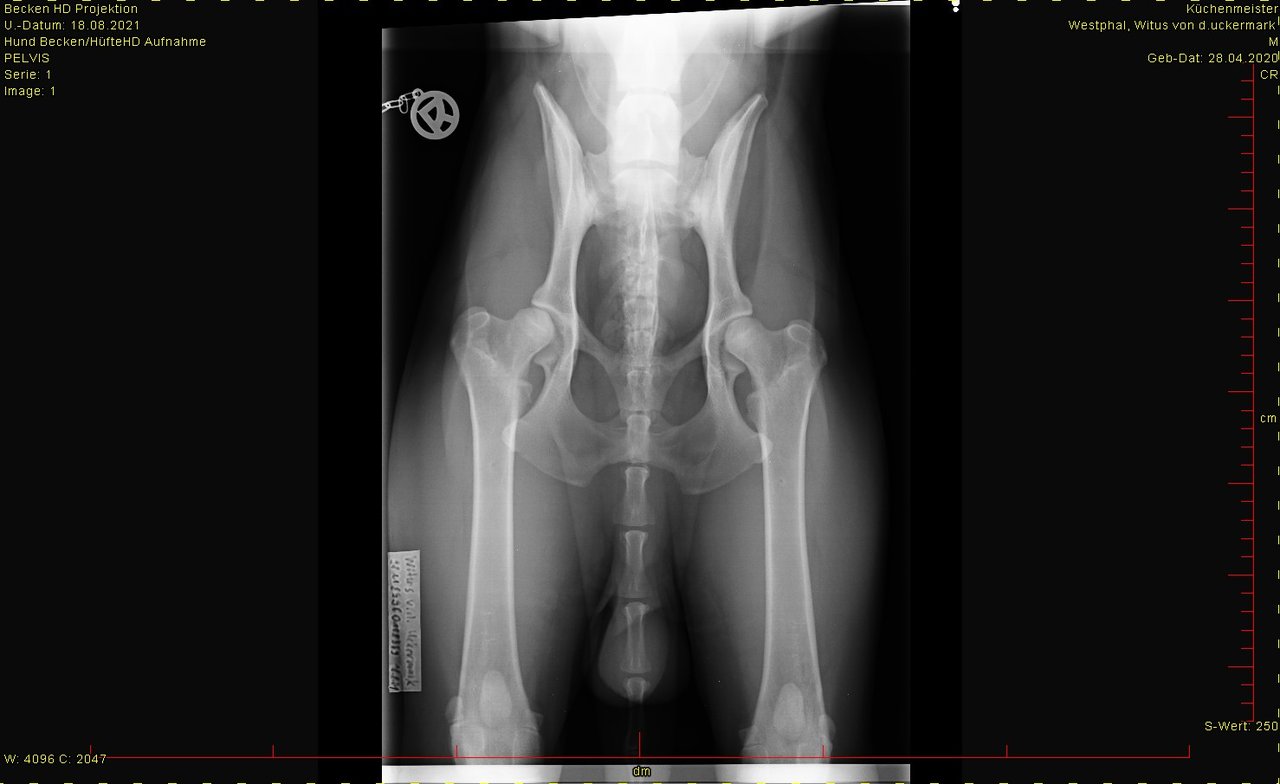

Die linke Hüfte wird wohl lt. TA eine leichte Abwertung bekommen. Was auch immer das heißt, HD fast normal? k.A. , mal sehen.

Jedenfalls kann man lt. der TA Hundesport mit ihm machen. Sie sagte auch, sie hätte schon viel schlechtere Hüften gesehen und diese Hunde wurden auch noch zugelassen. Ich hoffe mal, dass es wenigstens ein fast normal gibt.

Auf dem Bild sieht man ja beide Hüften und kann sie direkt miteinander vergleichen. Und dann sieht man gut die Unterschiede.

Aber wie gut sind die Hüften absolut gesehen? Das wird wohl Dr. Tellhelm dann beurteilen.

Für die offizielle Einstufung (normal, fast normal, usw.) zieht man immer die schlechtere Seite heran, nicht den "Mittelwert" beider Seiten.

Es kann gut sein, dass auf der linken Seite z.b. der Norberg-winkel nicht im Ideal liegt, sondern um ein paar Grad abweicht. Das gäbe dann ein "fast normal", das ist ja trotzdem ein super Ergebnis.

hier das Bild von der Hüfte. Ist HD-Aufnahme, kann man groß ansehen.

Was sagt Ihr dazu?

Bei den Ellenbogen traue ich mir keine Bewertung zu, finde aber, dass Hüfte und Rücken okay sind